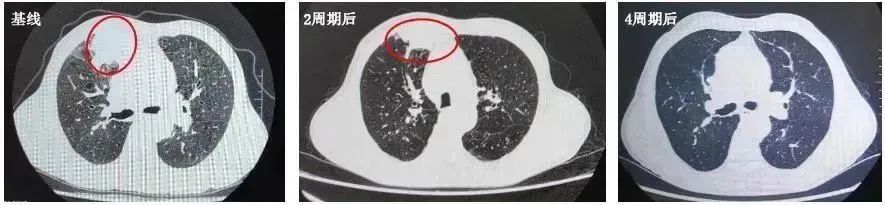

2022年5月11日-2022年7月30日:PD-1*制剂抑**+EC方案化疗共4周期,具体方案为:斯鲁利单抗(250mg,4.5mg/kg)+依托泊苷(0.16g d1-3)+卡铂(0.53g AUC5)。

2022年7月4日复查CT:与PACS20220421老片对比,现片示:1.右肺上叶前段不规则肿块灶(40mm×37mm)并纵隔多发肿大淋巴结明显缩小,上腔静脉受压变扁较前减轻:考虑周围型肺CA并纵隔淋巴结转移。2.双上肺、左下肺肺结核可能性大,CT表现为稳定性征象。3.慢性支气管疾患:肺气肿;肺大泡。

总体疗效评价为PR。

该例患者为广泛期小细胞肺癌患者,合并陈旧性肺结核,初诊伴有脑转移。2022年ASCO大会口头报道的ASTRUM-005研究中斯鲁利单抗有很好的疗效和安全性数据6,依据《2022年CSCO小细胞肺癌诊疗指南》,该患者一线使用斯鲁利单抗联合EC化疗方案进行治疗,治疗后咳嗽、声嘶较前明显好转,体力状况明显改善,生活质量明显提升。肿瘤标志物出现明显下降,且影像学检查提示肿瘤病灶出现明显退缩,疗效显著,且在治疗过程中未出现结核复燃。治疗期间患者未出现不可控的免疫不良反应,安全性良好。

该患者是一个基线伴有脑转移的广泛期小细胞肺癌患者,《2022年CSCO小细胞肺癌诊疗指南》推荐,对于无症状的脑转移小细胞肺癌患者,一线治疗推荐免疫联合化疗后,再行全脑放疗。此患者在进行4个周期斯鲁利单抗联合卡铂依托泊苷治疗后,影像学提示病灶明显退缩,脑转移病灶也明显缩小,疗效达到PR,充分证明斯鲁利单抗在广泛期小细胞肺癌患者中的良好疗效。